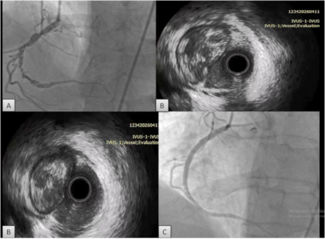

We decided to gain right femoral artery access in order to use a 7 Fr system to improve guiding catheter support, alignment, and to protect the LAD during performance of a certainly difficult procedure. The first angiogram showed the presence of a longitudinal compression of the ostial LAD stent (Figure 2B) probably due to the previous forceful withdrawal of the detached and jammed stent with secondary and involuntary deep guiding catheter intubation. We decided to wire the LCX and the LAD with BMW guidewires and, taking advantage of the longitudinal compression of the LAD stent, we were able to easily advance balloons and stents into the distal segments of the OM (Figure 3A). Then 2 non-overlapped Endeavor Resolute DES (2.5 mm x 18 mm an 2.75 mm x 24 mm) were delivered to the LCX without difficulties, resulting in a good final angiographic result with no further compromise of the ostial LAD stent.

We decided to gain right femoral artery access in order to use a 7 Fr system to improve guiding catheter support, alignment, and to protect the LAD during performance of a certainly difficult procedure. The first angiogram showed the presence of a longitudinal compression of the ostial LAD stent (Figure 2B) probably due to the previous forceful withdrawal of the detached and jammed stent with secondary and involuntary deep guiding catheter intubation. We decided to wire the LCX and the LAD with BMW guidewires and, taking advantage of the longitudinal compression of the LAD stent, we were able to easily advance balloons and stents into the distal segments of the OM (Figure 3A). Then 2 non-overlapped Endeavor Resolute DES (2.5 mm x 18 mm an 2.75 mm x 24 mm) were delivered to the LCX without difficulties, resulting in a good final angiographic result with no further compromise of the ostial LAD stent.

Finally balloon re-expansion of the DES longitudinal compression was performed with a Voyager (Abbott Vascular) 3.0 mm x 12 mm at 12 atm (Figure 3B), with complete resolution of the stent compression and a good final angiographic result (figure 3C).